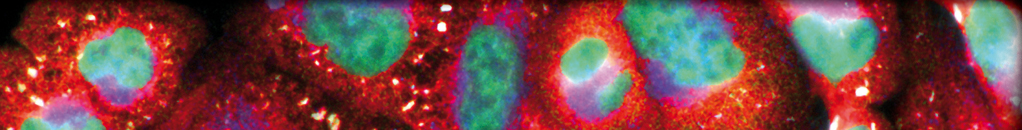

Inducible degrader of low-density lipoprotein (LDL) receptor (Idol) is an E3 ubiquitin ligase coded by Idol , the target gene of liver X receptor (LXR), which primarily mediates the ubiquitination...

Relevance: Inducible degrader of low-density lipoprotein (LDL) receptor (Idol) is an E3 ubiquitin ligase coded by Idol, the target gene of liver X receptor (LXR), which primarily mediates the ubiquitination and lysosomal degradation of low-density lipoprotein receptor (LDLR).